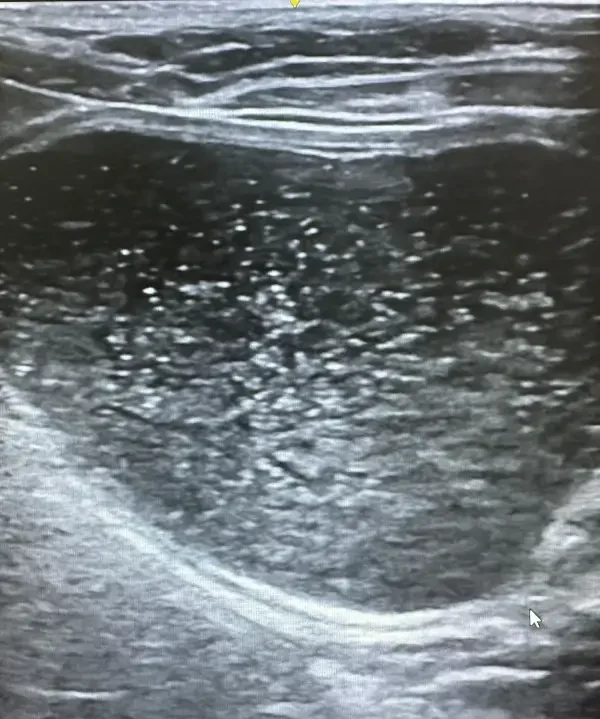

Ecografía abdominal y cardíaca: La ecografía es una técnica no invasiva que permite visualizar órganos internos en tiempo real, evaluando su estructura, tamaño y vascularización. A diferencia de la radiografía, no utiliza radiación y proporciona información sobre la arquitectura interna de los órganos.

Nuestro ecógrafo de alta gama con tecnología doppler color permite:

- Evaluación detallada de riñones, hígado, bazo, páncreas e intestino

- Diagnóstico de masas abdominales y diferenciación de su naturaleza

- Valoración de la vejiga y detección de cálculos urinarios

- Ecocardiografía para diagnóstico de cardiomiopatías

- Medición de flujos sanguíneos y evaluación de función valvular

La ecografía abdominal es especialmente útil en el diagnóstico de enfermedad renal crónica, permitiendo evaluar el tamaño, la ecogenicidad y la arquitectura renal. Podemos detectar quistes, cálculos renales, hidronefrosis y cambios estructurales indicativos de daño renal antes de que aparezcan síntomas clínicos.